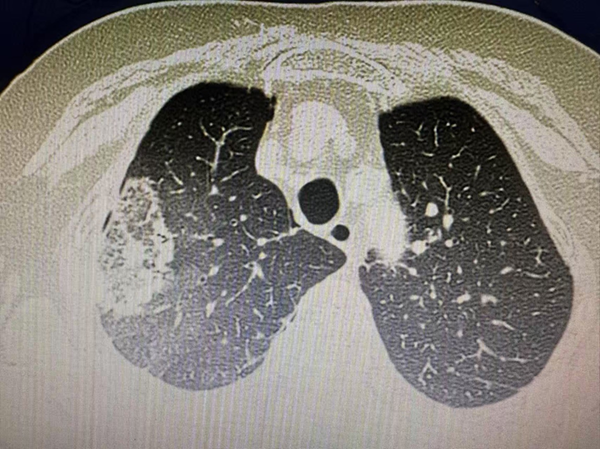

治疗后的CT改变

术前,胸外科组织影像科、麻醉科、急诊科等多科室开展MDT会诊,制定了多个应急预案,为手术做好万全准备。手术当天,胸外科团队为张奶奶实施了局部麻醉下冷冻消融手术,仅用时2小时,就完成了冷冻消融及组织活检。张奶奶说:“这么大的手术我都没什么感觉。”术后第二天复查双肺CT,达到预期效果,张奶奶当日便出院。